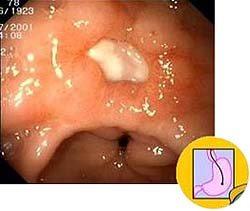

K26 Язва двенадцатиперстной кишки